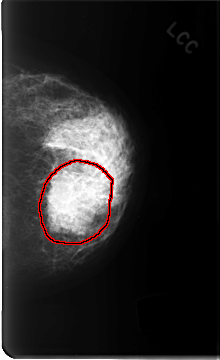

FILE: C_0343_1.LEFT_CC.OVERLAY

TOTAL_ABNORMALITIES 1

ABNORMALITY 1

LESION_TYPE MASS SHAPE OVAL MARGINS ILL_DEFINED

ASSESSMENT 5

SUBTLETY 5

PATHOLOGY MALIGNANT

TOTAL_OUTLINES 1

BOUNDARY